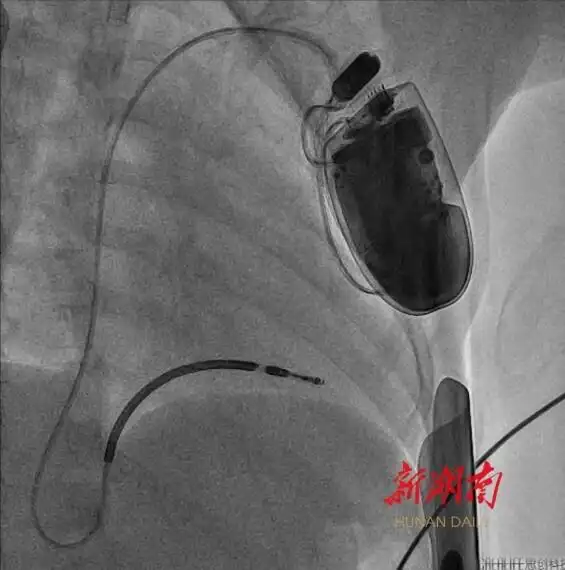

湖南日報4月22日訊(文字/視頻 全媒體記者 周陽樂 通訊員 黃娟 宋青青)今天,記者從湖南省兒童醫(yī)院獲悉,該院血管內(nèi)科陳智主任團隊近期成功為一名年僅4歲半、體重16公斤的短QT間期綜合征患兒植入心臟轉(zhuǎn)復律自動除顫器(ICD)。此為中南地區(qū)年齡最小、體重最低的兒童心臟轉(zhuǎn)復律自動除顫器手術(shù)案例。

“悅悅在ICU住了近1個月,進行電除顫治療七八十次,十分揪心。”王野峰說,為確保悅悅的生命安全,醫(yī)院組織心血管內(nèi)科、ICU、麻醉手術(shù)科、影像科團隊進行多學科聯(lián)合評估,最終決定為其實施ICD植入術(shù)。“ICD是一種用于治療嚴重心律失常的醫(yī)療設(shè)備。當患者發(fā)生室性心動過速、心室撲動或心室纖顫等嚴重心律失常時,ICD通過電極感知這些異常心律,并通過電復律或起搏等方式迅速終止心律失常,確?;颊叩纳踩?rdquo;

體重輕、血管細小、皮下脂肪薄……術(shù)前,團隊對手術(shù)路徑設(shè)計、導管操作方式、麻醉方案及術(shù)中突發(fā)狀況處理等細節(jié)進行了嚴密論證。4月16日上午,在麻醉師全程監(jiān)護下,團隊結(jié)合血管超聲的特點,成功經(jīng)腋靜脈,將電極導線精準送達右心室心尖部,并通過調(diào)整預留適合孩子生長的長度,經(jīng)程控測試確認最佳起搏閾值后,與ICD裝置完成精準連接。

經(jīng)過2個小時的努力,手術(shù)順利結(jié)束。術(shù)后,護理團隊為悅悅制定了個性化護理方案,重點防控感染、導線移位等風險,通過多學科協(xié)作保障醫(yī)療安全。目前,悅悅恢復狀況良好,未再出現(xiàn)室顫發(fā)作。